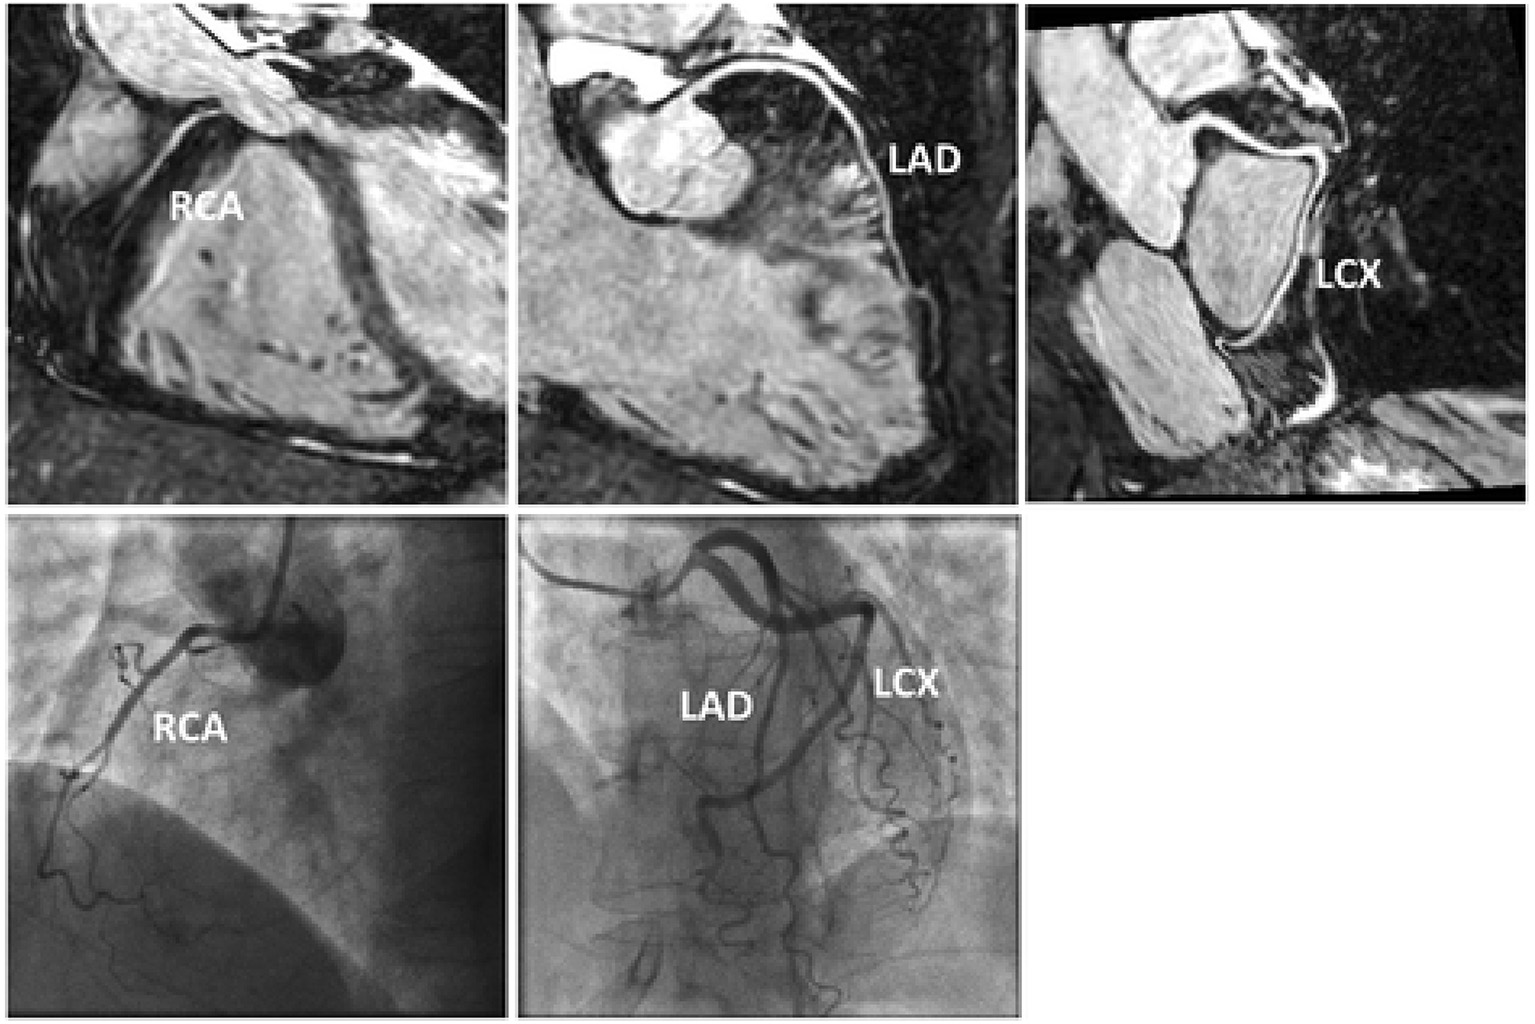

However, with 1D self-navigation, it is difficult to separate moving (e.g., heart) from static (e.g., chest wall) tissue, which introduces artefacts (47). Image-based navigators (iNAVs) are an alternative platform to respiratory self-navigation. Whilst offering up to 100% respiratory scan efficiency, the principle aim of iNAVs is to separate moving tissue from static tissue by acquiring a low spatial resolution 2D/3D image at every heartbeat prior to the acquisition of high resolution CMRA (47–51). This framework also enables the capability to estimate respiratory motion in multiple directions to factor in the multidimensional motion of the heart. Furthermore, it eliminates additional planning as the iNAV can be derived within the same field of view (FOV) and orientation as the CMRA planning. An early version of iNAV CMRA framework demonstrated highly diagnostic image quality in the proximal, middle and distal coronary segments (98, 94, and 91, respectively) (Figure 2) (52). The sensitivity, specificity, and negative predictive values were 86, 83, and 95% per patient, 80, 92, and 97% per vessel and 73, 95, and 98% per segment; compared with X-ray coronary angiography.

Figure 2

Reformatted CMRA datasets (top row) from a patient without coronary artery disease but non dominant RCA. Coronary x-ray angiography in the same patient (bottom row). RCA, right coronary artery; LAD, left anterior descending artery; LCX, left circumflex artery. Adapted with permission from Henningsson et al. (52).